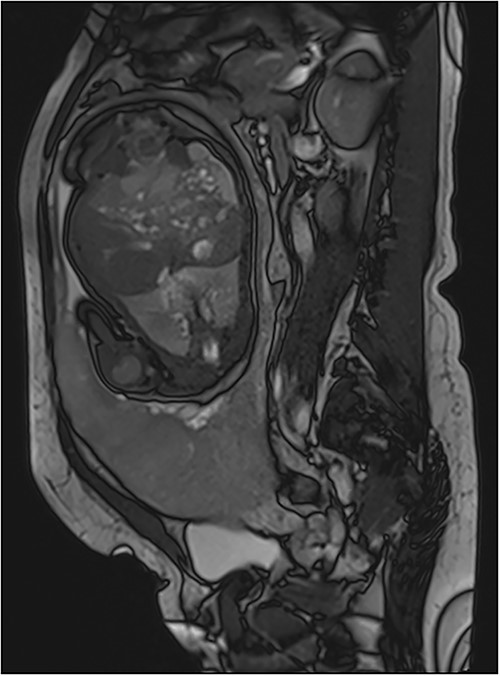

In the case of placenta percreta (like ultrasound), we might have dark intra-placental bands on T2-WI with a heterogenous appearance of the placenta and abnormal disorganized placental vascularity seen as traversing vessels. There’s also focal interruptions of the myometrial wall and the most particular sign in placenta percreta is the tenting of urinary bladder with the involvement of uterine serosa or extra-uterine involvement of adjacent organs like bladder, rectum or abdominal wall [9] (Fig. 5).

Trufisp T2 sagittal-WI of a 44-year-old patient in our department showing the invasion of the urinary bladder.